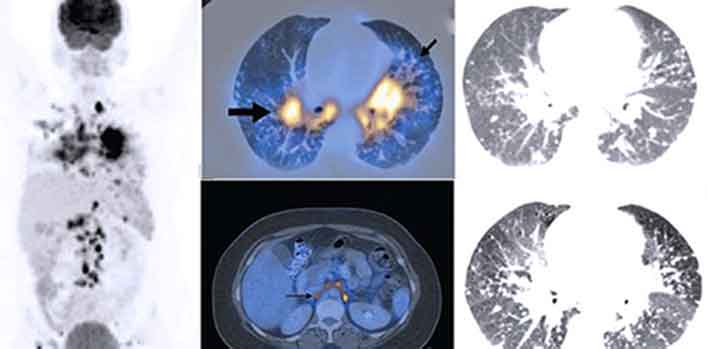

Гиперфиксация рфп при пэт кт

Гиперфиксация рфп при пэт кт 140 фото